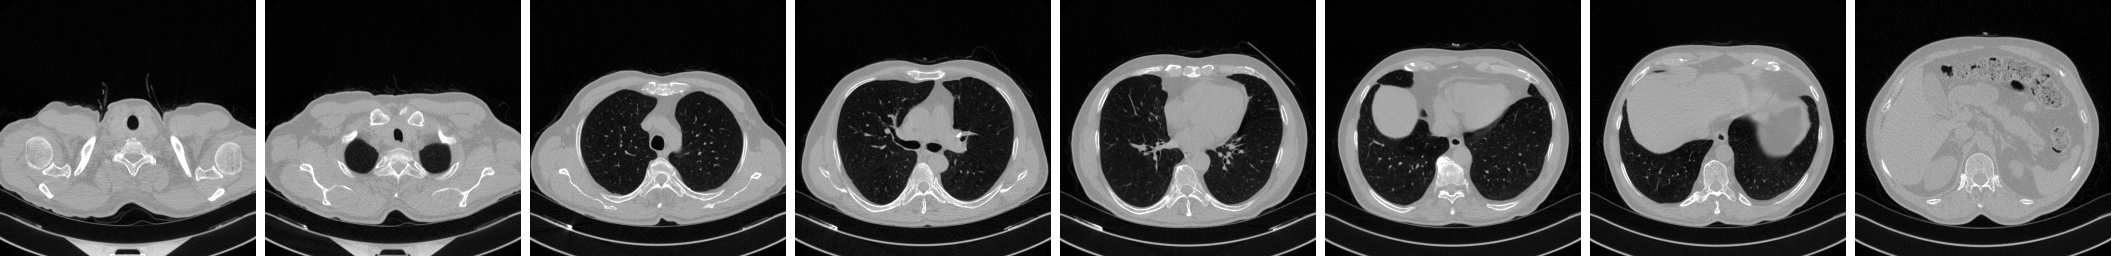

A new dataset (IST-C) is collected at Istanbul University-Cerrahpaşa, Cerrahpaşa Faculty of Medicine (IUC), consisting of 712 chest CT scans collected from 645 patients. It includes samples from COVID-19 infected patients, as well as normal lung parenchyma and Non-COVID-19 pneumonia, tumors and emphysema patients. Figure 1 shows three samples from the IST-C dataset collected in this work, including a typical COVID-19 involvement pattern termed as ground glass opacity, along with normal lung parenchyma and other conditions including non-COVID-19 pneumonia, tumors and emphysema.

Sample images extracted from COVID-19, ”Normal” and ”Other” classes are shown in Figure 1. The anonymized dataset is now shared publicly at http://github.com/suverim.

Lung shapes vary greatly within a chest CT scan, as can be seen in Figure 1. With the aim of focusing on the lung areas, we used the pretrained U-Net network to segment lung regions from non-lung areas.